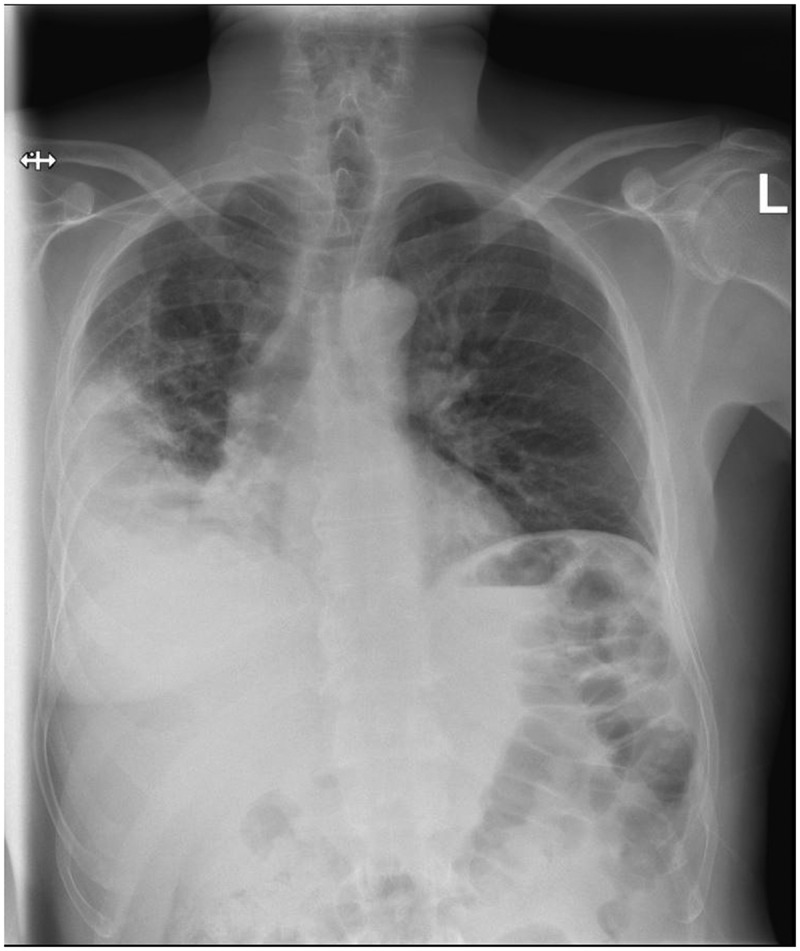

Serotype 3 pneumococcal infection can cause severe invasive disease, even in immunocompetent adults, and is potentially preventable by vaccination. Invasive pneumococcal disease caused by serotype 3 is currently the most frequent serotype found in adults in Denmark. In this report, we present a 62-year-old immunocompetent man diagnosed with a severe pleural empyema caused by serotype 3, requiring a long course of antibiotics. The patient experienced clinical improvement, and follow-up imaging showed near-complete resolution of lung infiltrates. We also review the epidemiology of serotype 3 invasive pneumococcal disease in adults in Denmark and discuss the challenges related to serotype 3 and effective vaccines.